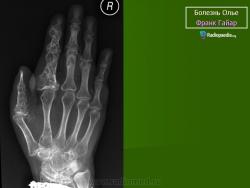

ОЛЛЬЕ СИНДРОМ (описан французским хирургом L. Ollier, 1830–1900; синоним – энхондроматоз, остеохондроматоз) – системное нарушение развития скелета, при котором на ранних этапах эмбриогенеза нарушается трансформация хряща в костную ткань; в растущей кости сохраняются очаги необызвествленной хрящевой ткани, что приводит к деформации и укорочению костей. Возможно поражение 1 (монооссальная форма заболевания), 2–3 (олигооссальная форма заболевания), 4 и более (полиоссальная форма заболевания) костей; поражаются преимущественно метафизы длинных трубчатых костей, фаланги пальцев, тазовые кости. Проявления заболевания возникают в возрасте 2–10 лет и зависят от локализации и тяжести процесса. Изменения обычно двусторонние, но асимметричные. При локализации процесса в нижних конечностях наблюдаются хромота, перекос таза, вальгусная или варусная деформация и прогрессирующее укорочение ног. При поражении верхних конечностей характерны лучевая или локтевая косорукость, выраженная деформация пальцев. Возможны патологические переломы. Нередко наблюдается малигнизация с развитием хондросаркомы. В редких случаях сочетается с гемангиомами мягких тканей (синдром Мафуччи). Диагноз уточняют при рентгенологическом исследовании, выявляющем четкие очаги овального или веерообразного просветления в метафизах длинных трубчатых костей. Тип наследования – предположительно аутосомно-доминантный. Лечение: выравнивание длины нижних конечностей с помощью ортопедической обуви, в случае выраженных деформаций показана хирургическая коррекция.

Клиническая картина. Заболевание выявляется в раннем детском возрасте, с началом ходьбы появляются деформации костей, хромота, прогрессирующее укорочение конечностей. Нередко первым проявлением болезни служат патологические переломы измененной кости; гемангиомы (при синдроме Мафуччи).Рентгенологически трубчатые кости умеренно или значительно укорочены, эпиметафизы булавовидно расширены, вздуты; в метафизах определяются очаги просветления неоднородной структуры.

Болезнь Олье.

Клиническая картина. Заболевание выявляется в раннем детском возрасте, с началом ходьбы появляются деформации костей, хромота, прогрессирующее укорочение конечностей. Нередко первым проявлением болезни служат патологические переломы измененной кости; гемангиомы (при синдроме Мафуччи). Рентгенологически трубчатые кости умеренно или значительно укорочены, эпиметафизы булавовидно расширены, вздуты; в метафизах определяются очаги просветления неоднородной структуры.